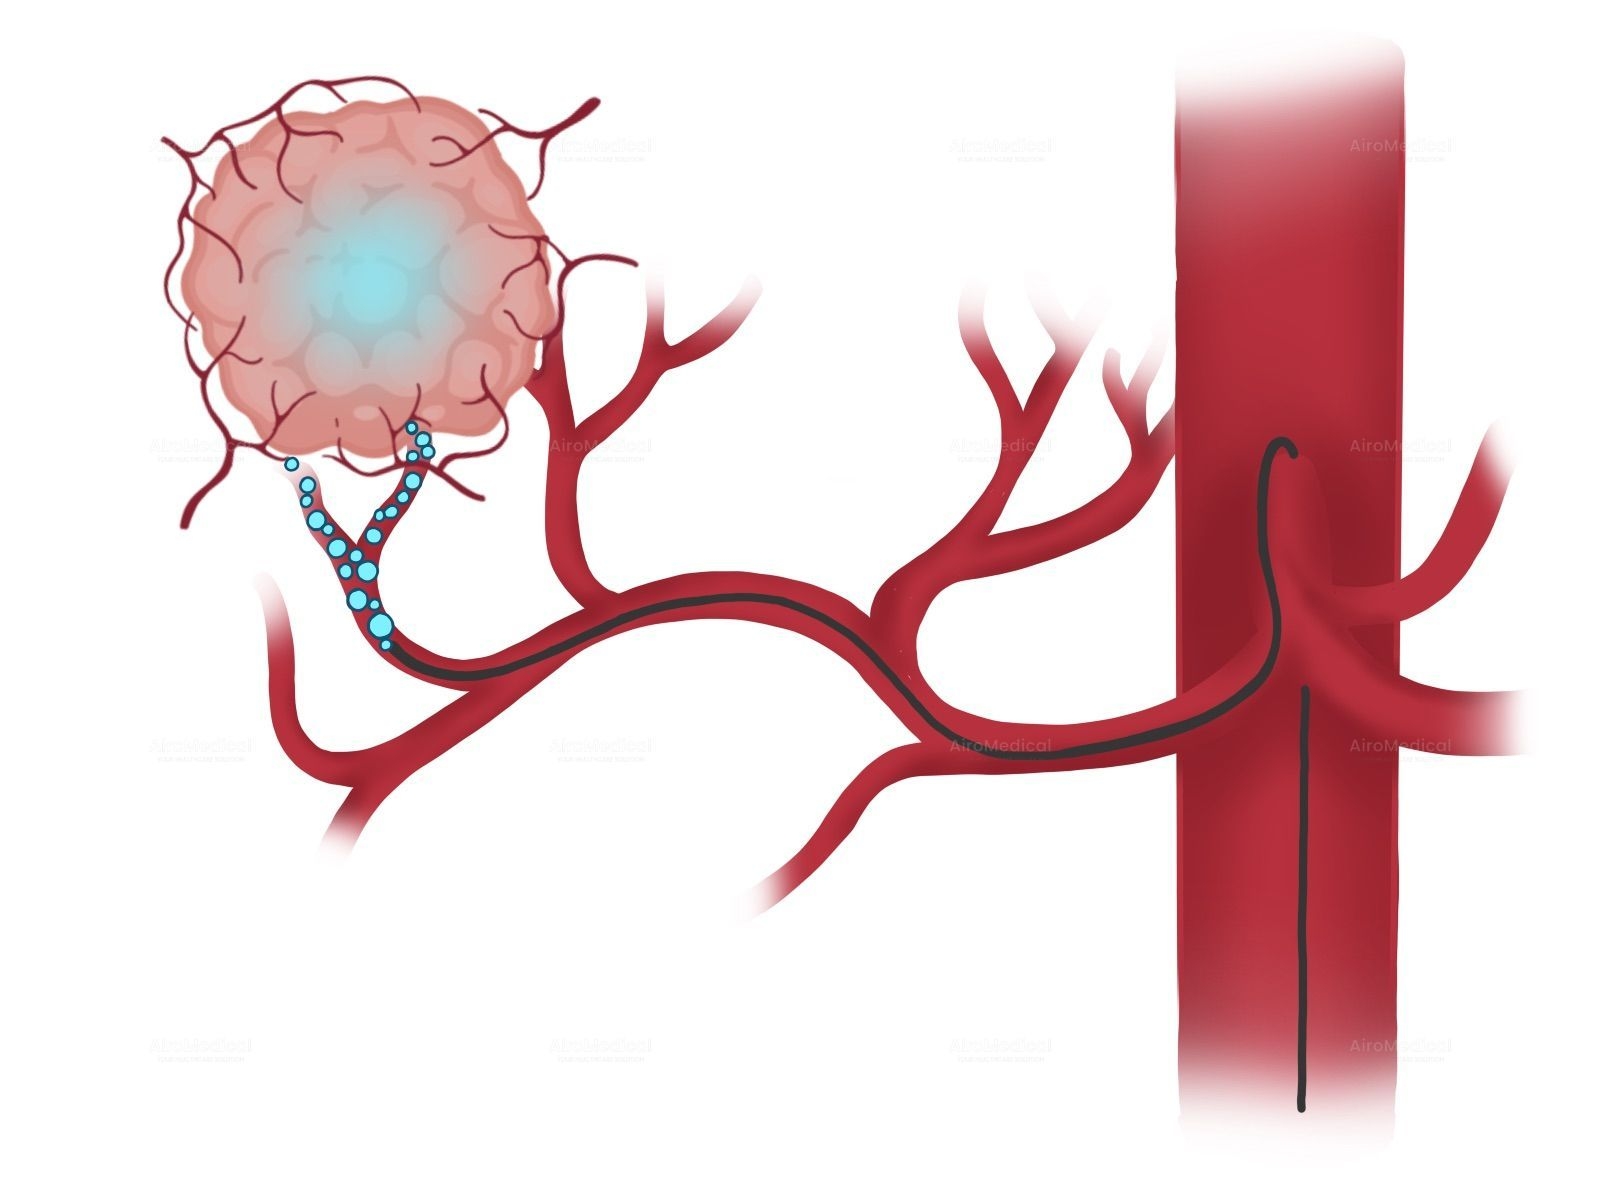

Is University Hospital Frankfurt suitable for patients with cancer?

It is one of the largest institutions dealing with cancer treatment. The oncology unit has a spiral tomograph, a gamma knife, PET, and other latest-generation equipment. Moreover, the team has performed hundreds of successful operations to treat the most complex oncological diseases.